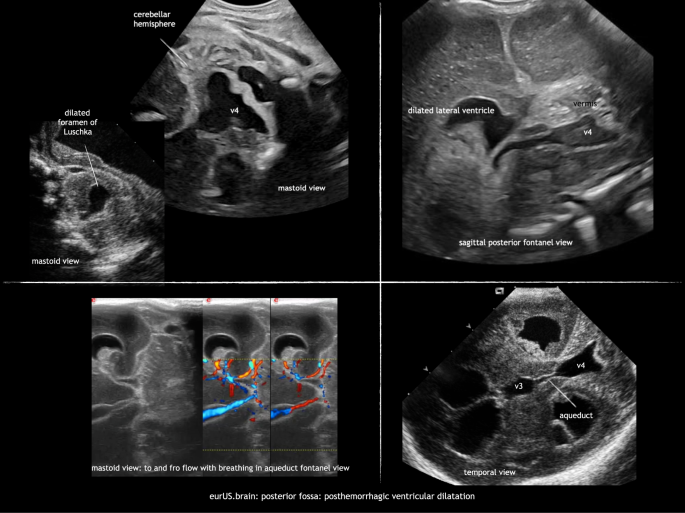

Ventricular dilatation can occur as a sequela of GMH-IVH or intracranial infection. It is due to obstruction by a clot or subependymal scarring at the level of the foramen of Monro, aqueduct, fourth ventricle exit foramina, or cerebellar arachnoid spaces. Scanning through the MF visualizes the ventricular system and locates the site of obstruction. A dilated aqueduct—in some with to and fro motion on Doppler exam—and/or fourth ventricle can be visualized by ultrasound (Fig. 8). When both the inflow and outflow of the fourth ventricle are obstructed, this can lead to a severely dilated trapped fourth ventricle, with brainstem compression. This requires a specific therapeutic approach.